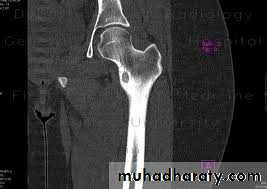

is pathognomonic. There is a

well-defined exostosis emerging from the metaphysis,its base co-extensive with the parent bone.

It looks smaller than it feels because the cartilage cap is usually invisible on x-ray.

The x-ray appearance